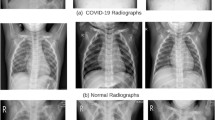

Introduction: The provision of medical facilities needed for COVID-19 diagnosis is a global concern. They must be a powerful tool for detecting and diagnosing the virus quickly using a variety of tests, as well as low-cost advancements. Whereas a chest X-ray image is an effective screening technique, the image acquisition by the instruments must be read appropriately and quickly if multiple tests are performed.

Objectives: COVID-19 causes continuous respiratory parenchymal ground glass and integrates respiratory opacity, with a curved shape and peripheral pulmonary dissemination in some cases, which is difficult to anticipate earlier on. In this chapter, we intend to construct a good platform to identify COVID-19 characteristics from the image of chest X-ray to aid in early analysis.

Methods: In particular, based on the Cuckoo search method, this chapter provides a bioinspired CNN-based model for COVID-19 diagnosis. This method identifies different deep learning strategies of COVID-19 patients’ chest X-ray images for accurate infection identification. The suggested model’s performance is estimated using the Cuckoo search approach. Furthermore, the bioinspired CNN characteristics are fine-tuned using optimization algorithm. Rigorous testing reveals that suggested method may accurately categorize chest X-ray images with high performance, remembrance, and sensitivity. Results: As a result, the suggested approach can be used to classify COVID-19 diseases from chest X-ray images in real time and also accuracy will be validated.